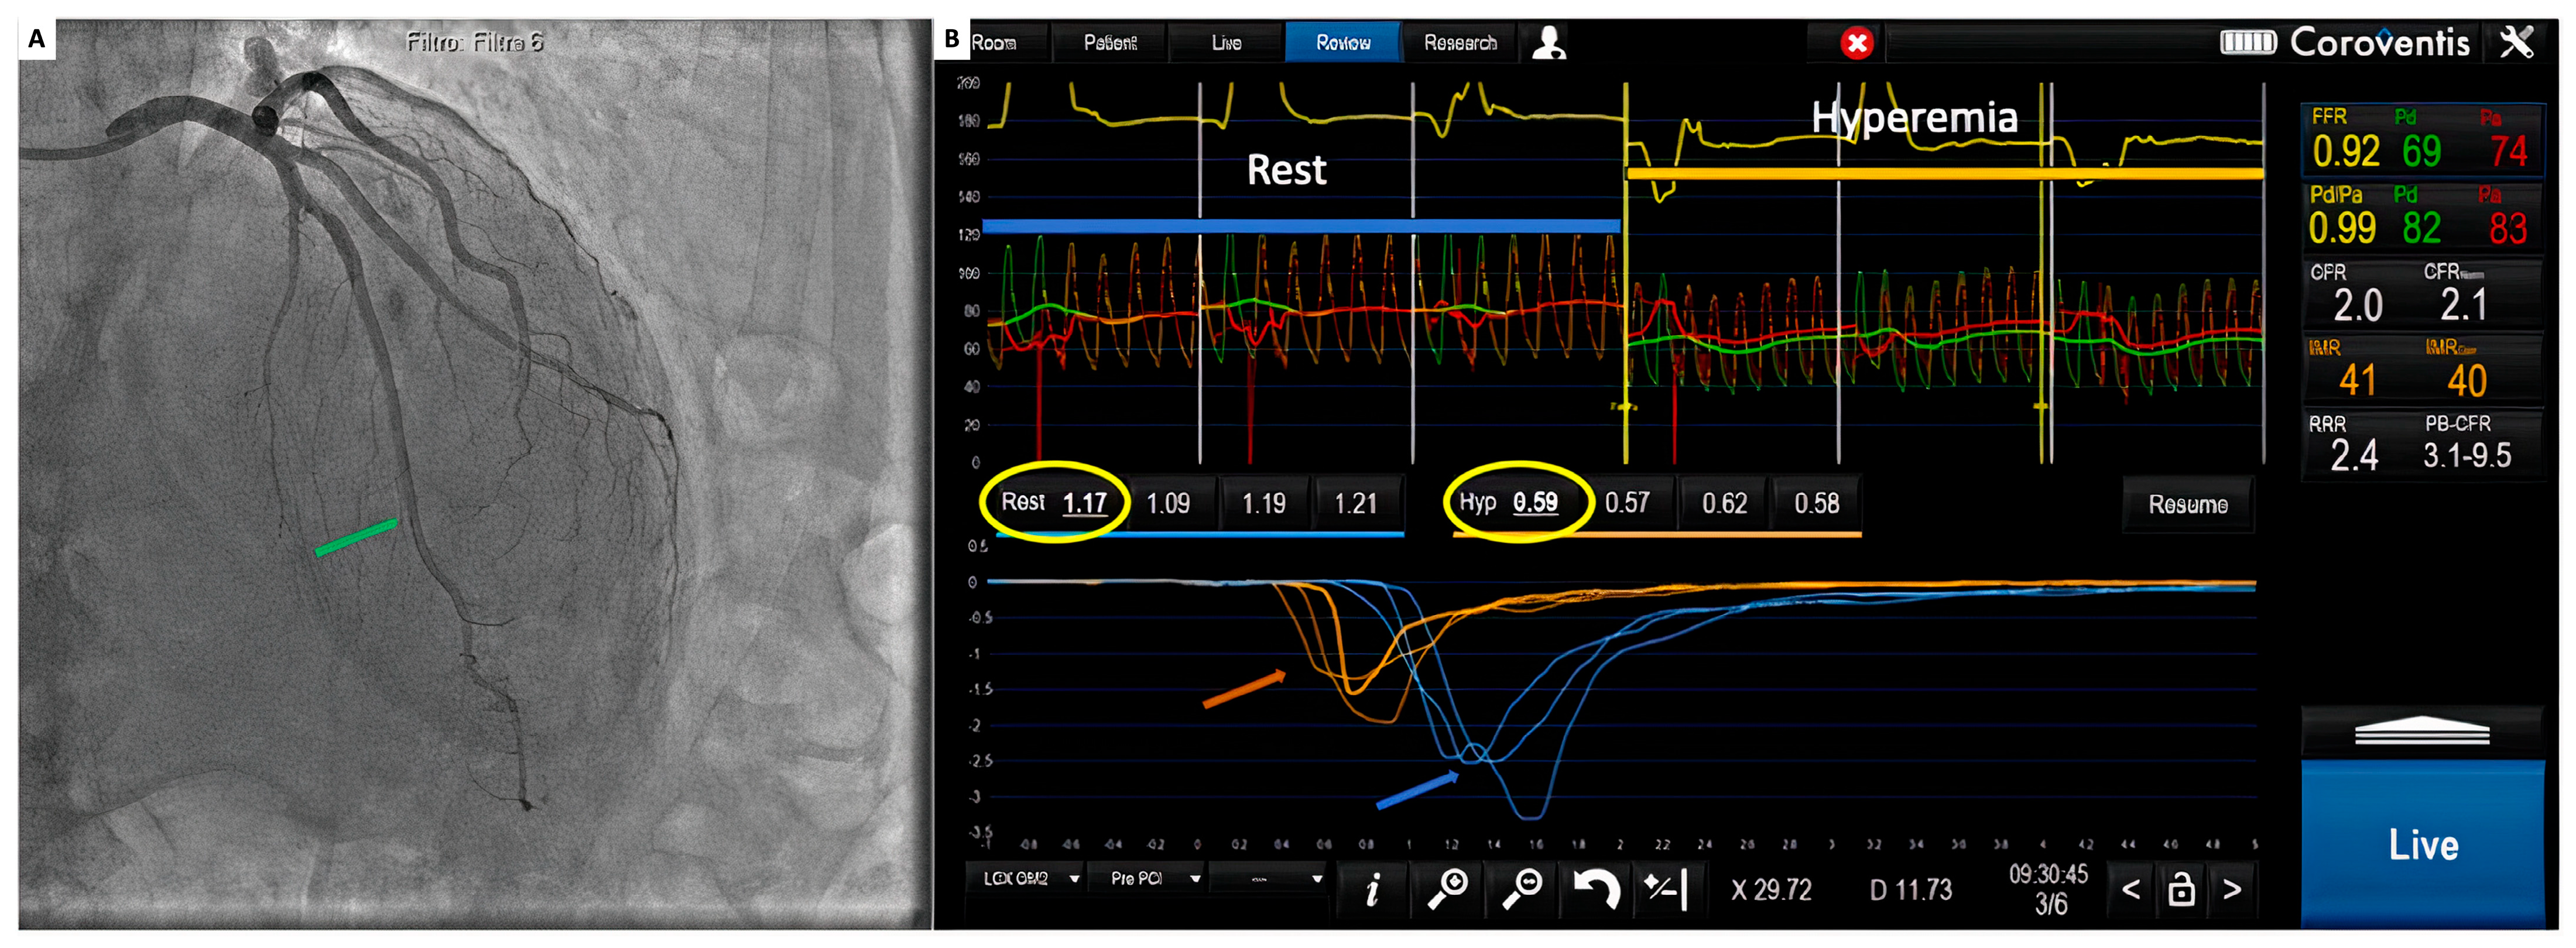

With a 6 Fr guiding catheter positioned in the coronary ostium, a 0.014″ floppy pressure–temperature coronary guidewire is advanced through the coronary artery, after equalization, and located as distal as possible into the target vessel. Thermodilution curves can be obtained with a short manual injection of 3 to 5 mL of saline at room temperature, and a time-based temperature change can be recorded in the distal part of the artery (Figure 4).

Figure 4.

(A) Coronary angiogram. Green arrow: pressure wire sensors; (B) coroventis interface during invasive functional assessment. Red and green pressure tracings represent, respectively, aortic (Pa) and distal coronary pressure (Pd). Blue arrow: intracoronary temperature variation of 3 consecutive boluses of saline at rest. Orange arrow: intracoronary temperature variation of 3 consecutive boluses of saline during maximal hyperemia. Yellow circles: average mean transit time values at rest (Rest) and during hyperemia (Hyp).

Because of the low reproducibility, measurements must be performed three times, taking care not to move the wire during the injections, during two different periods: at baseline and during maximal hyperemia [50].